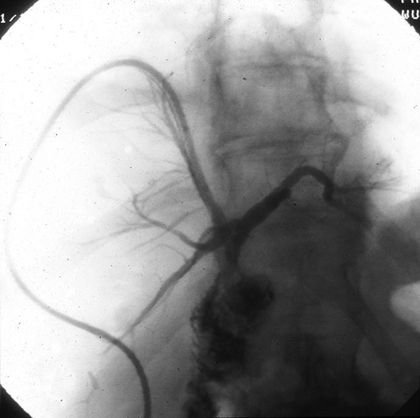

Since a leaking bile duct can be fatal, it's important to see a doctor if you experience symptoms The role of the radiologist and interventional radiologist is important in the diagnosis and treatment of such. Corrective treatments can help close the biliary tree opening and stop the leak.

Bile is a fluid made by the liver that is important for digestion. What is a biliary leak A biliary leak occurs when bile leaks out of any of the ducts that transport bile to the small intestine Bile is made in the liver and secreted to help digest fats